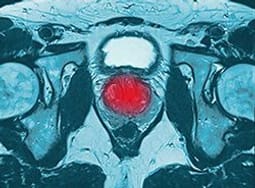

Achados De Imagem Na Ressonancia Magnetica Multiparametrica Dos Leiomiomas Prostaticos Puros